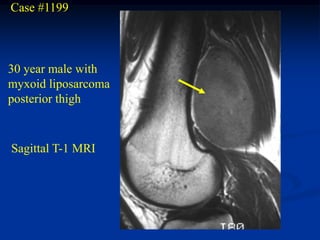

Case #1199

30 year male with

myxoid liposarcoma

posterior thigh

Sagittal T-1 MRI

Case #1199 30 yearmale with myxoid liposarcoma posterior thigh Sagittal T-1 MRI